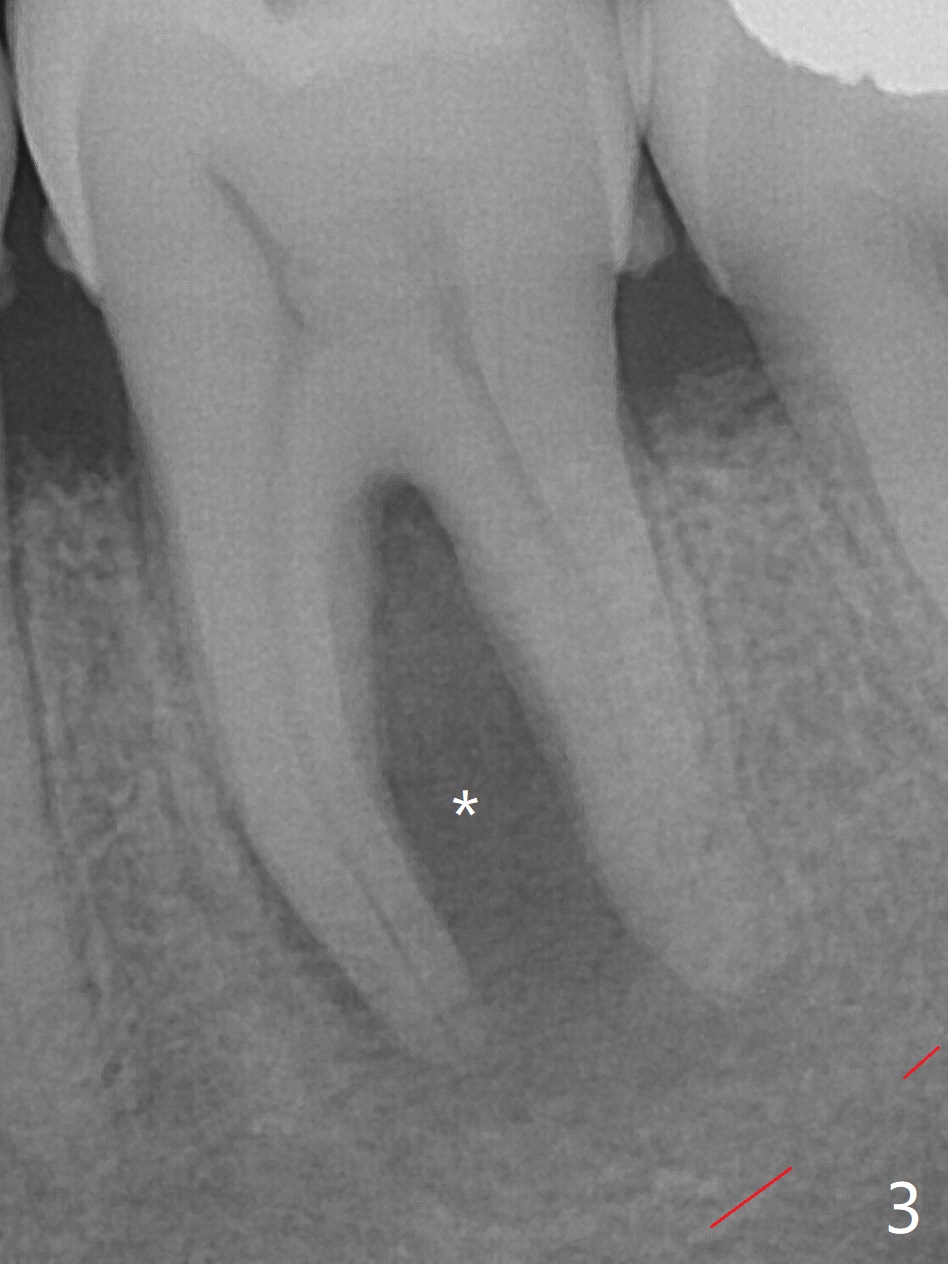

A 62-year-old man (smoker, 1.5 packs a day) has had no dental visit for 12.5 years (Fig.1). His chief complaint is pain at #19 after eating popcorn. The septal bone resorbes (Fig.2,3 *) with granulation tissue between the mesial and distal roots (Fig.4,5 *). Although there is no bony wall defect, the socket is single and large (9x9 mm, Fig.7). The largest (8 mm) cylindrical implant should not be able to obtain primary stability. The biggest challenge for immediate implant is ambiguous the Inferior Alveolar Canal (Fig.1,3 red dashed line). If there were no financial or time issue for immediate implant, CBCT should have been taken. Socket preservation is done instead with Vanilla graft, Human Amniotic Chorion Allograft (membrane) and Osteogen Plug (Fig.6). If he returns for SRP and implant, perform flapless bone expansion for osteotomy. When the patient returns 14 d postop, #19 socket is healing and filled with bone graft (Fig.8 (panoramic X-ray)). When he returns 14 months postop, the socket heals (Fig.9, as compared to Fig.6).